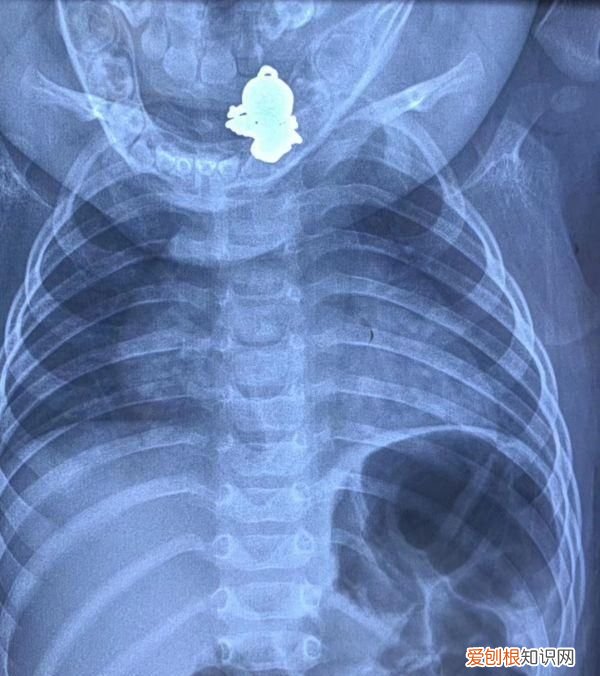

【解雨臣的四只吞金兽分别是谁 9个月的吞金兽吞下个金宝宝】嘟嘟吞下的“金宝宝” 。图由医院提供

按照医生的建议,家长先观察了3天,吊坠没能自行排出,只好带着孩子到武汉儿童医院求助 。检查显示,吊坠卡在孩子食道入口处 。随后,耳鼻咽喉科张亚敏医生做急诊手术取出了吊坠 。因为吊坠外形不规则,嘟嘟的食道入口处有轻微划伤、出血 。

拍片显示,吊坠卡在嘟嘟食道入口处 。图由医院提供